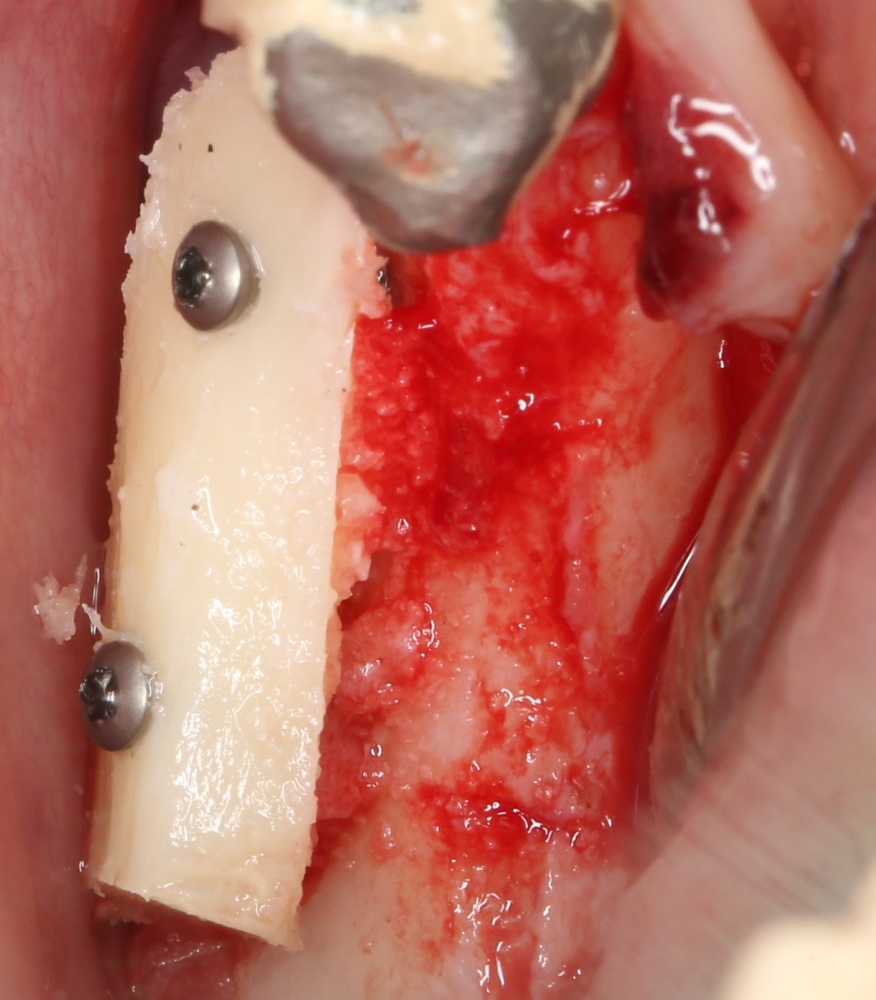

Подготовка костного ложа и фиксация аутотрансплантата

Возвращаемся к основной операционной области. Еще раз посмотрим на альвеолярный гребень, поофигеваем от его ширины и моих грандиозных планов:

Я зафиксировал костный блок практически без адаптации на несколько винтов. Обрати внимание, что винты находятся в зоне, где не планируется установка имплантатов. Фиксация должна быть надежной, поскольку мне еще предстояла подготовка лунок для имплантатов. Трех винтов для этого вполне достаточно.

Дальнейшая адаптация костного блока свелась к сглаживанию острых краев. После чего я приступил к подготовке лунок и установке имплантатов.